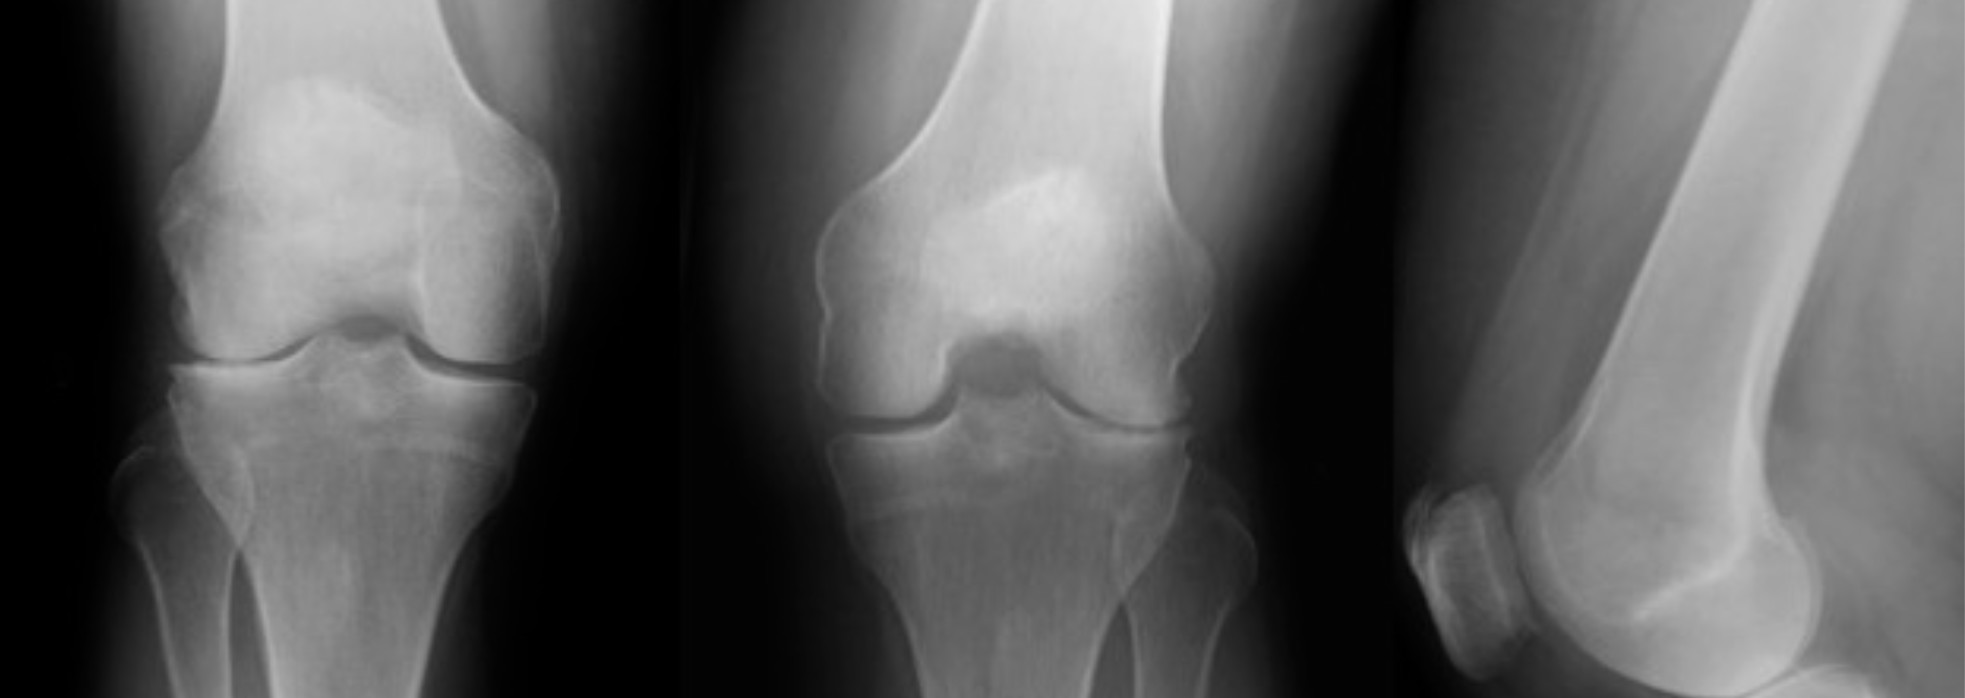

The bones of the knee are the femur, or thigh bone. The tibia, or shin bone. The fibula, the little long bone on the outside of the leg. The patella, or knee cap, that is in the front of the knee and is located inside the tendon of the quadriceps and patella tendon. Bones provide the structural support of the body and where bones connect and motion occurs we call this a joint.

The bones of the knee are the femur, or thigh bone. The tibia, or shin bone. The fibula, the little long bone on the outside of the leg. The patella, or knee cap, that is in the front of the knee and is located inside the tendon of the quadriceps and patella tendon. Bones provide the structural support of the body and where bones connect and motion occurs we call this a joint.

The white, smooth, surface coating on the ends of the bones where two bones meet and move is called cartilage. This cartilage is made up of many cell layers oriented in different directions that provide its different functions. This surface provides painless smooth motion, resistance to shear forces, and shock absorption between the bone ends.

The knee joint is the location where the end of the thigh bone and the top of the shin bone and fibula meet. All of the structures in this location make up the knee joint. The knee joint moves smoothly in healthy knees because of the coating on the end of the bones called cartilage. The Knee joint has three main compartments.

- The Medial Compartment is the inner side of the knee joint between the thigh bone (femur) and shin bone (tibia). Medial compartment is the most common compartment that wears down in the knee and the most common location for partial knee replacement. Partial knee candidates have pain with weight-bearing in just the medial compartment.

- The Lateral Compartment is on the outer side of the knee joint between the thigh bone (femur) and shin bone (tibia). The lateral compartment is the second most common compartment that wears down in the knee. Lateral compartment partial knee candidates have pain with weight-bearing in just the lateral compartment.

- The Patellofemoral Compartment is the third compartment of the knee. This is the compartment in the front of the knee between the kneecap (patella) and the thigh bone (femur). The patella moves down the middle of the two knuckles (condyles) on the end of the femur and increases the efficiency of the quadriceps muscle. Patients with pain in the patellofemoral compartment often describe pain with rising and sitting, stair climbing and knee bending. Patellofemoral partial knee candidates have pain in the anterior compartment under the kneecap (the front of the knee), but no pain in the medial or lateral joint compartments.